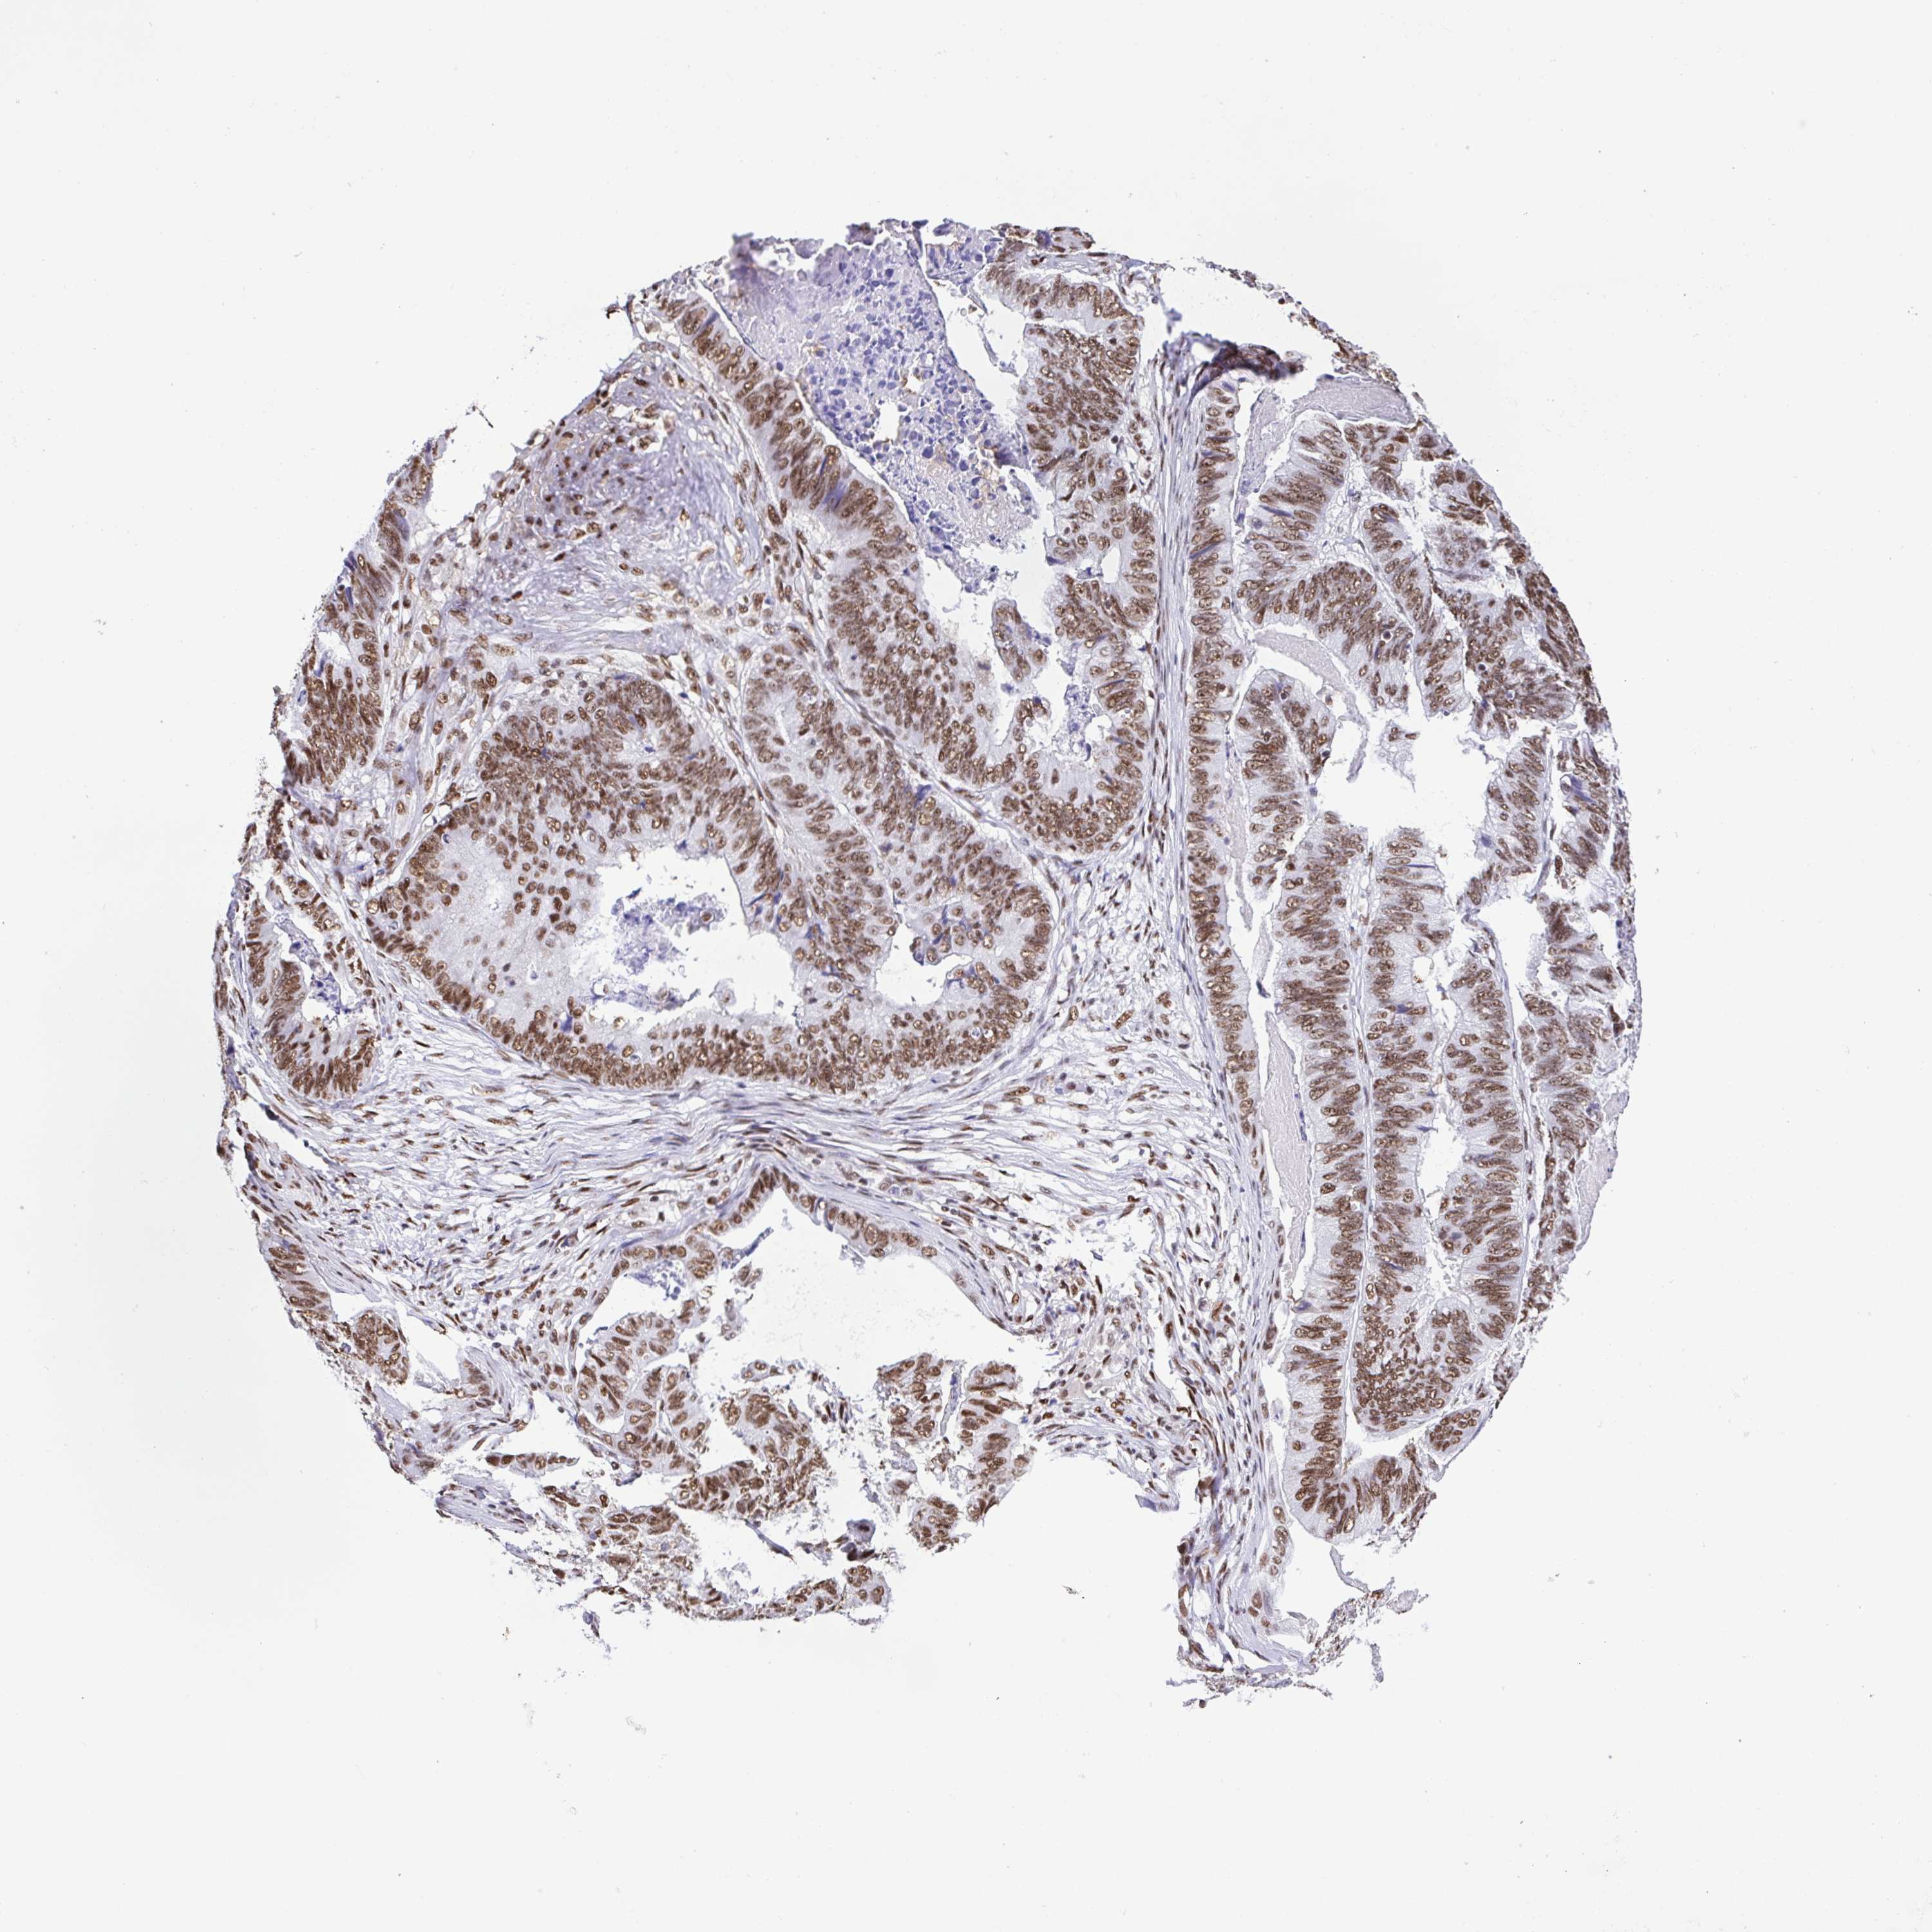

STOMACH CANCER - Protein expressioni

A mouse-over function shows sample information and annotation data. Click on an image to view it in a full screen mode. Samples can be filtered based on level of antibody staining by selecting one or several of the following categories: high, medium, low and not detected. The assay and annotation is described here.

Note that samples used for immunohistochemistry by the Human Protein Atlas do not correspond to samples in the TCGA dataset.

Antibody stainingi

Antibody staining in the annotated cell types in the current human tissue is reported as not detected, low, medium, or high, based on conventional immunohistochemistry profiling in selected tissues. This score is based on the combination of the staining intensity and fraction of stained cells.

Each image is clickable and will lead to virtual microscopy that enables deeper exploration of all samples and also displays staining intensity scores, fraction scores and subcellular localization as well as patient and tissue information for each sample.

Antibody HPA064033

Antibody CAB010066

Staining

High

Medium

Low

Not detected

Intensity

Strong

Moderate

Weak

Negative

Quantity

>75%

75%-25%

<25%

None

Location

Nuclear

Cytoplasmic/membranous

Cytoplasmic/membranous,nuclear

Adenocarcinoma, NOS

Adenocarcinoma, High grade